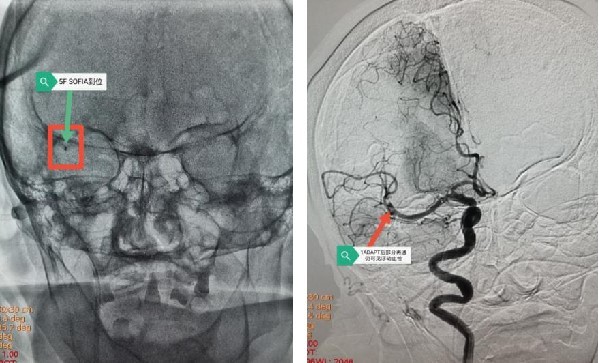

手术由张冬子执行院长带队、卒中中心李伟旺主任、陈斌副主任医师和杜乐乐住院总医师共同完成 。 造影显示“Ⅲ型弓” , 迂曲成角明显 , 交换技术无法将导管输送到位 。 危情时刻 , 脑组织濒临死亡 。 卒中团队讨论后 , 果断行颈动脉穿刺置鞘 , 之后行云流水般顺利将颅内血栓完全取出 , 快速恢复了颅内血流!术后30分钟患者肌力明显改善!之后使用专用血管封堵器完美封堵颈动脉穿刺点 。

取栓后血管成像示:右侧大脑中动脉完全再通

患者能转危为安 , 得益于我院高效的卒中急救绿色通道 , 在非常短的时间内将堵塞的血管开通 , 挽救了大量濒临死亡的脑细胞 , 为后期神经功能恢复奠定基础 。 为了积极防治脑卒中 , 提高脑卒中的救治水平 , 最大限度地降低致残和死亡率 。 脑科医院整合了神经内科、神经外科、急诊科、影像科、介入科、康复科、检验科的优势医疗资源 , 打破学科界限 , 以急性脑血管病为中心 , 全流程陪检 , 实现多学科无缝对接 , 为赢战卒中争分夺秒 。